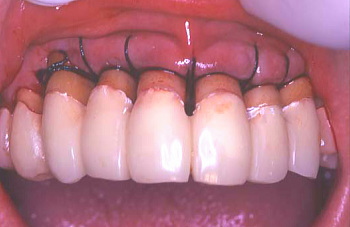

⑩ 歯肉を閉じて縫合した状態。

⑪ 歯肉縫合後仮り歯を入れた状態。

⑫ その上に歯周パック(歯周包帯)を張った状態